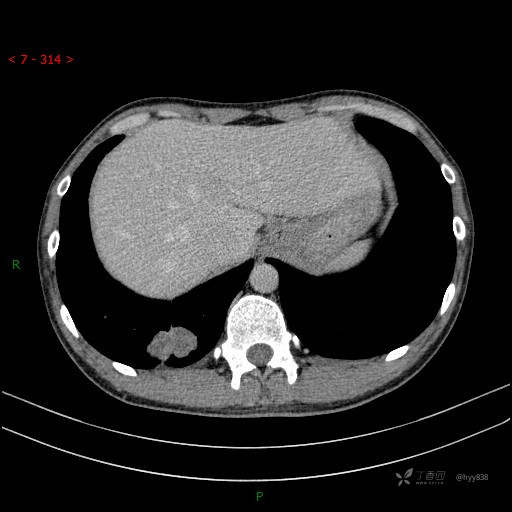

静脉期